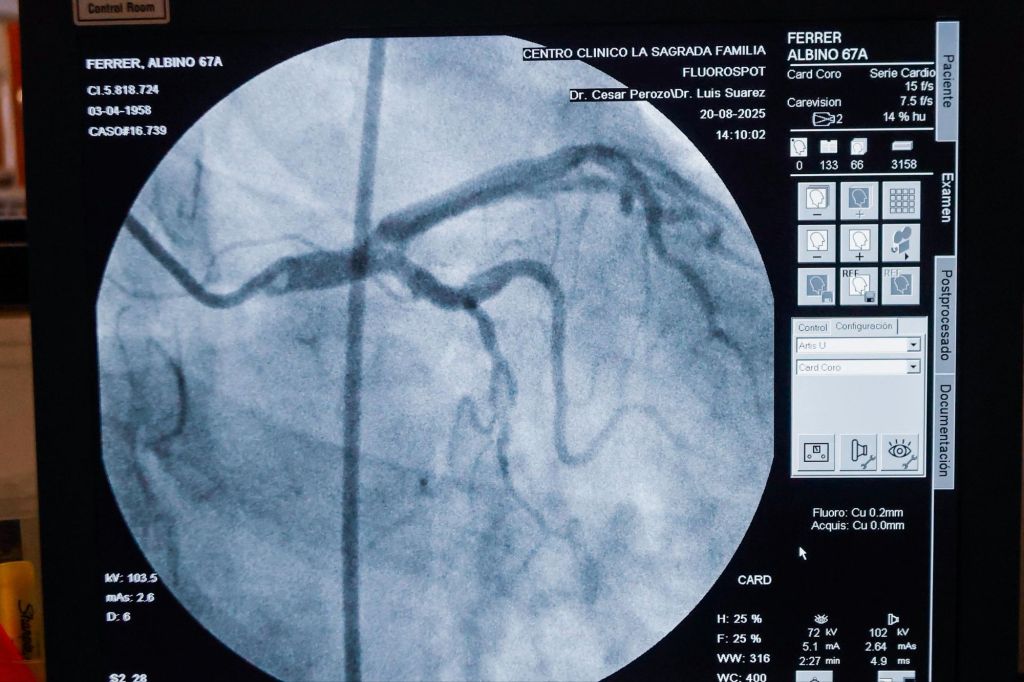

El jefe del gobierno zuliano informó desde este centro, que en el inicio de este plan fueron atendidos el primer día 11 pacientes, continuando hasta cumplir con los 80 ya captados en esta primera fase de resolución de patologías, en algunos casos que ameritan cateterismo, cateterismo con angioplastia y colocación de Stent, entre otras.

Manifestó el gobernador que los casos son atendidos por un equipo de expertos de la ciencia zuliana, coordinado por el doctor César Perozo Wong, en este centro clínico de referencia en la Cirugía de Cardiología a nivel internacional y nacional, bajo alianza con la Gobernación.

“En esta fase de caracterización de los casos hemos conseguido algunas complejidades, como unas que ameritan una revascularización, así como otros de cirugía de corazón abierto”, refirió.